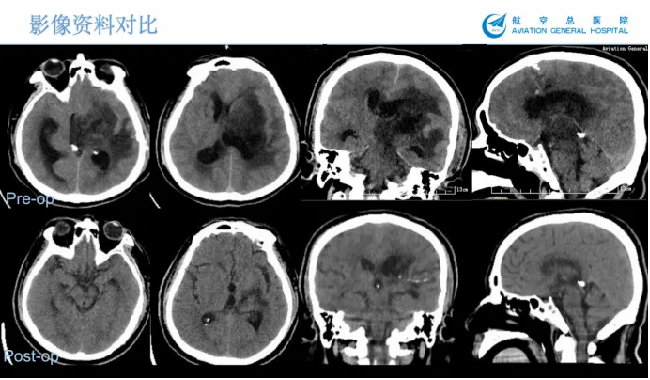

张先生的不幸始于一次脑出血,导致他开车途中陷入昏迷并伴有呕吐。被路过的好心人发现,紧急送往石家庄某医院,头颅CT检查揭示了问题的严重性——左侧基底节区脑出血破入脑室。情况危急,当地医生迅速采取双侧脑室外引流术。术后一周,张先生逐渐恢复意识,脑出血也开始吸收,但失语和右侧肢体偏瘫的症状仍旧困扰着他,大小便失禁,生活的每一分钟都离不开家里人的照顾。随着时间的推移,张先生的意识和状态再次出现了下滑,检查显示脑室扩张和脑肿胀的迹象,预示着新的挑战正悄然而至。医生们决定进行左侧基底节区穿刺引流术,暂时稳定了他的状况。但是,这也不过是缓兵之计。拔除引流管后,他的状态并未得到根本改善。6月7日的复查结果令人揪心——脑积水的问题依旧存在。

为了更深入地解决问题,张先生被转入航空总医院接受更为系统和全面的治疗。在脑出血、脑积水治疗上拥有丰富经验的肖庆主任,提出患者目前具有包括颅内出血后脑积水、间质性脑水肿、中枢神经系统感染等一系列复杂情况,以及由脑出血引发的偏瘫、失语等后遗症。

面对这一挑战,肖庆主任和科室团队没有放弃。他们决定采用更为直接的方法来解决脑积水问题。6月9日,张先生接受了软性神经内镜检查及血肿清除术、透明隔造瘘术、侧脑室外引流术等一系列复杂手术。术后,医生们发现患者脑脊液中有柠檬色明串珠菌、粘质沙雷菌感染,痰培养提示铜绿假单胞菌,肖庆团队给予针对性地抗感染治疗,同时纠正了他的电解质失衡和糖尿病问题。

软性神经内镜治疗后,脑脊液中红细胞、白细胞、蛋白等指标均有明显好转,加快病情恢复的进程经过持续的努力,张先生脑脊液化验合格,关管多日可以耐受。7月21日,分流管终于被成功拔除。随后的检查显示,张先生的脑室未见扩张,病情稳定。在整个治疗过程中,康复医学科和中医科的参与为张先生的恢复增添了新的动力。床旁康复治疗帮助他逐步恢复了肢体功能,中医治疗则在调理身体方面发挥了重要作用。

头颅CT检查是颅内血肿有效、迅速的确诊方法。临床上通常根据头颅CT检查所见,动态跟踪颅内血肿的变化情况。发病初期,新鲜血肿表现为均匀一致的高密度(CT片上呈白色),随着血肿内血红蛋白分解,其密度逐渐降低(CT片上病灶的颜色逐渐由白色向黑色转变),直径不超过2cm的血肿一般在3周或更早就变成等密度,而大的血肿常需4-6周才能演变为等密度。但CT所见的血肿缩小,只是根据高密度逐渐变为等密度来判断,而实际上此时血凝块大小变化不大,并没有真正地吸收。

近年来,随着神经内镜技术的日益成熟,内镜下脑室探查所见使得人们对颅内血肿的吸收状况有了新的认识。经神经内镜技术探查发现脑室内仍有大量陈旧血斑,说明至少经过5个月血肿仍没有完全吸收。这些血肿的破坏产物对脑组织会持续产生一系列继发性损害。由此可见,颅内出血后尽早清除血肿,减轻继发性脑损害,有助于远期神经功能的恢复。